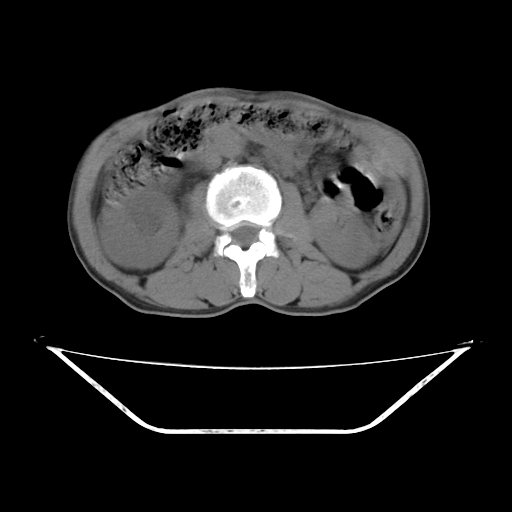

平扫

考虑右肾盂癌,肾动脉受侵,右肾功能减退,右肾盂输尿管积水,管壁增厚,考虑种植转移,应该把下面扫完的

支持右侧肾盂癌伴肾静脉瘤栓形成可能性大,右肾结石.肝右叶后段低密度影,不除外转移.

右肾盂旁ca并肾静脉瘤栓形成/肾功能降低。

右肾结石。

右肾盂癌,肾动脉受侵,右肾盂输尿管积水,管壁增厚,考虑种植转移

支持 右侧肾盂癌伴肾静脉瘤栓形成可能性大,右肾结石;肝右叶后段低密度影,不除外转移。

1.右侧肾盂癌伴肾盂积水。

2.肾脏功能减退,原因有:(1)肾动脉受侵。(2)肾静脉受侵(3)肾积水,等。本例,肾动脉显影较好,但受压明显;肾静脉无明显显示,受压或静脉癌栓,下腔静脉腔内未见明显充盈缺损。

3.右侧上段输尿管扩张,原因:(1)积水所致;(2)种植。